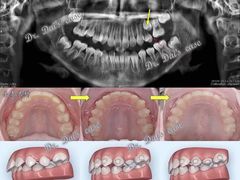

• 岳辰齿科(浦东长泰店)

• -岳辰齿科(浦东长泰店)

青青 | 23-11-12